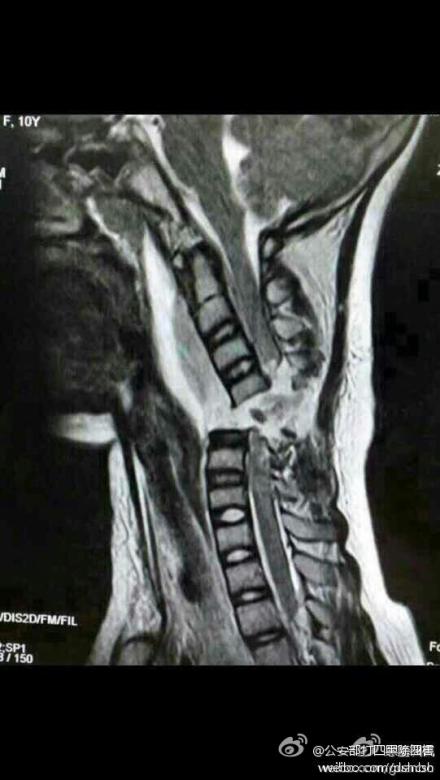

受伤的这名女孩家住邯郸。昨日早上,在家人的无比焦急中,女孩小青被紧急送至省三院就诊。经过专家们的仔细诊断和全面会诊,小青的颈椎已经完全断裂,这意味着小青很可能会高位截瘫。

专家们通过询问得知,导致这一悲剧的原因是小青在乘坐电动车时,由于其所佩戴的围巾较长而被绞进电动自行车车轮里。“12月2日下午,小青戴着长围巾乘坐电动车时,长围巾被车轮绞住。在惯性作用下,小青的脖子被紧紧勒住,电动车停下后,小青感觉自己不能动了,而且呼吸也变得非常困难。”专家们说,小青随即被送至当地医院进行紧急抢救,可由于其病情较重当地医院遂建议其到石家庄就医。

当小青被送到石家庄时,距悲剧已发生了15个小时,一轮紧张有序的检查后,小青被送进医院手术室。不幸中的万幸,手术进行得很成功。但由于脊柱断裂,小青的全身已瘫痪。同时,意外还影响到了肌肉,小青已经不能自主呼吸,目前只能通过呼吸机辅助呼吸。